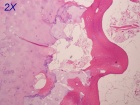

19 year old female with history of a right distal femur mass that is not growing, but has recently become painful

Zoom image: Cell stain Cell stain.